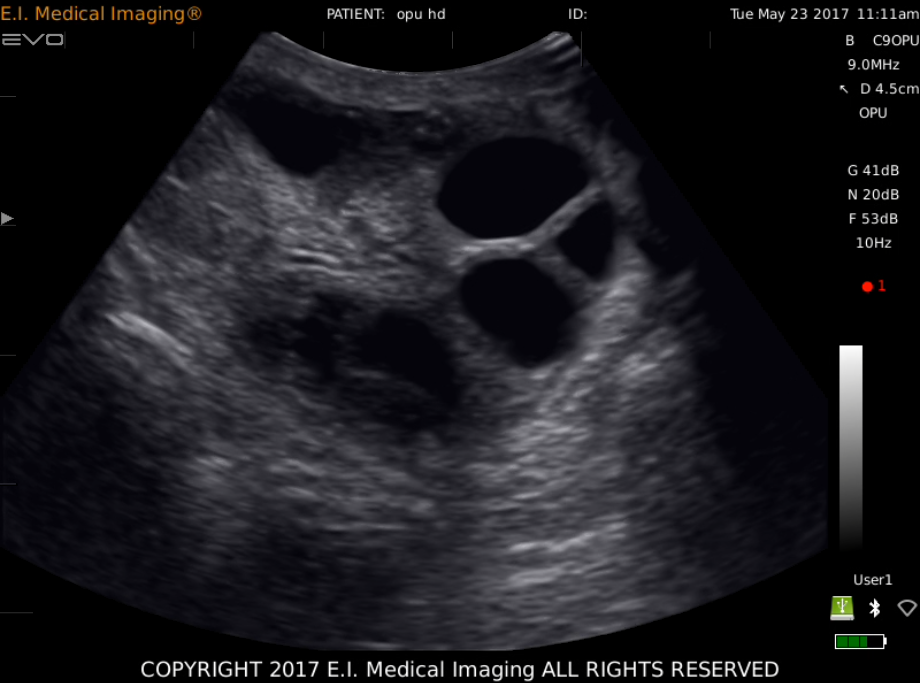

产品影像图

• 牛卵巢卵泡

2、操作人员一手拿探头一手通过直肠对卵巢进行牵引,把卵巢牵引到贴在探头上,使得我们能在EVO显示屏上清楚的看到卵巢,根据图像区分卵泡和CL,调整B超探头和卵巢的位置使监视器上卵泡位于穿刺针直线的延长线上时,推进穿刺针对卵泡进行穿刺.同时,用脚踏开关控制真空泵抽取卵泡液,真空泵的压力在60~80mm汞柱之间调整。

3、从监视器上可以观察到被抽取卵泡液和卵泡开始缩小,变得不规则,黑色的影像变成了亮片,直到卵泡在图像上消失,退出穿刺针,再对第二个卵泡进行穿刺,抽取卵泡液,直到该侧卵巢上2ram以上的卵泡被穿刺完后,调整探头以相同的方法对另一侧卵巢的卵泡进行穿刺。最后,所有符合条件的卵泡都被穿刺完后,用含有肝素的PBS液冲洗采卵针及导管,冲洗液也方入收集管。